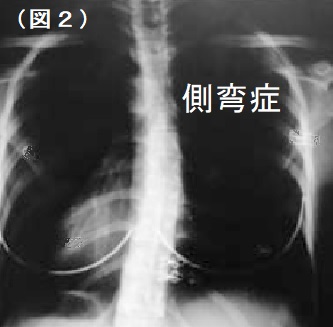

また、肩こりになる人は、加齢とともに増加傾向にありますが、小・中学生でも成長期に背骨が横に

湾曲してしまう側弯症が原因で肩こりや腰痛など発症する場合もあります。